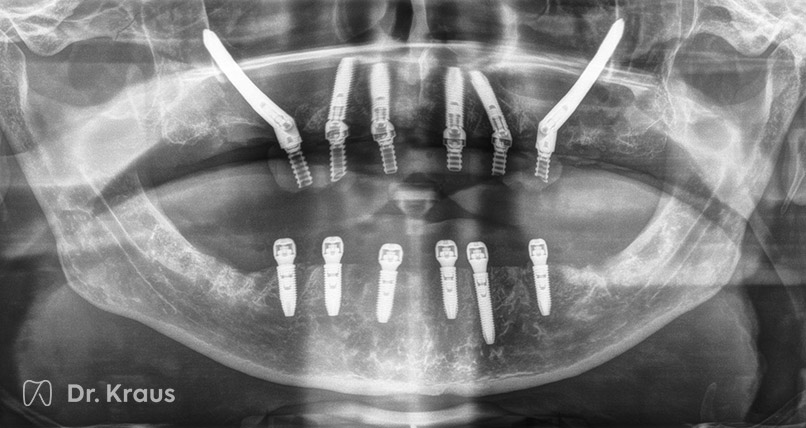

Patientenfall 43

Ausgangssituation

Stark zerstörte Zähne, Zahn- und Wurzelreste. Patient hat starke Zahnarztangst und war lange nicht beim Zahnarzt.

Behandlungsmaßnahmen

Entfernung der nicht erhaltungswürdigen Zähne. Implantation von insgesamt sechs Implantaten im Oberkiefer, davon zwei auf Grund der nicht ausreichenden Knochensituation im hinteren Kieferbereich als Zygoma-Implantate. Implantation von sechs Implantaten im Unterkiefer. Sofortige Versorgung mit festem, verschraubtem Zahnersatz (Langzeit-PV).